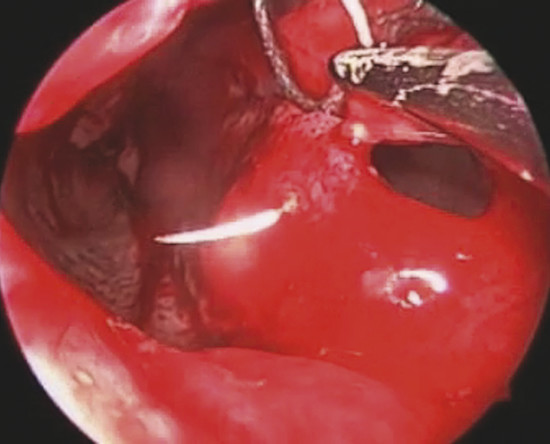

The mucoperiosteal graft is then inserted through the hemitransfix incision in the tunnel between the septal cartilage and elevated septal mucoperichondrial flap (Fig. 19‑8).

Graft borders are positioned under the previously elevated perforation borders in underlay fashion for minimum 5 mm all around (Fig. 19‑9).

At the end of this step, no one area of the perforation has to be uncovered (Fig. 19‑10).